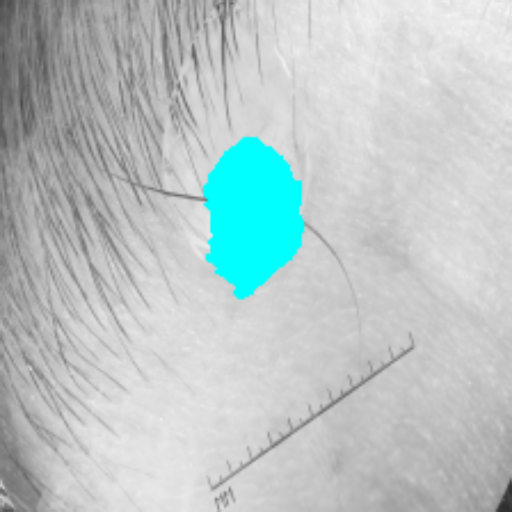

Figure 3 presents a qualitative comparison of segmentation performance on examples from the Synapse, BTCV, ACDC, and ISIC17 datasets. The first two examples (from Synapse) highlight variations in segmentation performance among U-Net, TransUnet, Mamba-Unet, and Swin-Unet. While Swin-Unet performs well in the first example, its performance decreases in the second example, particularly in segmenting the organ highlighted in blue. Additionally, it misclassifies background regions as the class highlighted in orange. In contrast, our approach demonstrates high robustness in segmenting all classes accurately and aligning well with the ground truth masks.

Across BTCV, ACDC, and ISIC17, the comparison methods exhibit varying performance depending on the task and class. For instance, Mamba-Unet struggles to segment multiple organs in BTCV, even misclassifying certain classes as others. In the ACDC dataset, both TransUnet and Mamba-Unet perform poorly in segmenting the three classes. In the last column (ISIC17), Swin-Unet oversegments the skin lesion compared to the ground truth. Unlike the comparison models, our approach consistently delivers effective segmentation across different tasks and datasets.

These qualitative findings further reinforce the quantitative results presented in the experimental section, demonstrating the effectiveness of our MambaCAFU model in handling binary and multi-class segmentation across diverse medical imaging modalities and tasks.

Slice GT Unet TransUnet Mamba-Unet Swin-UMamba MambaCAFU-V1

Figure 3: Visual comparison of segmentation examples from Synapse (first two examples), BTCV (3-4 examples), ACDC (5th example) and ISIC17 (last example). Columns: input slice, ground truth, Unet, TransUnet, Mamba-Unet, Swin-UMamba, and MambaCAFU-V1.